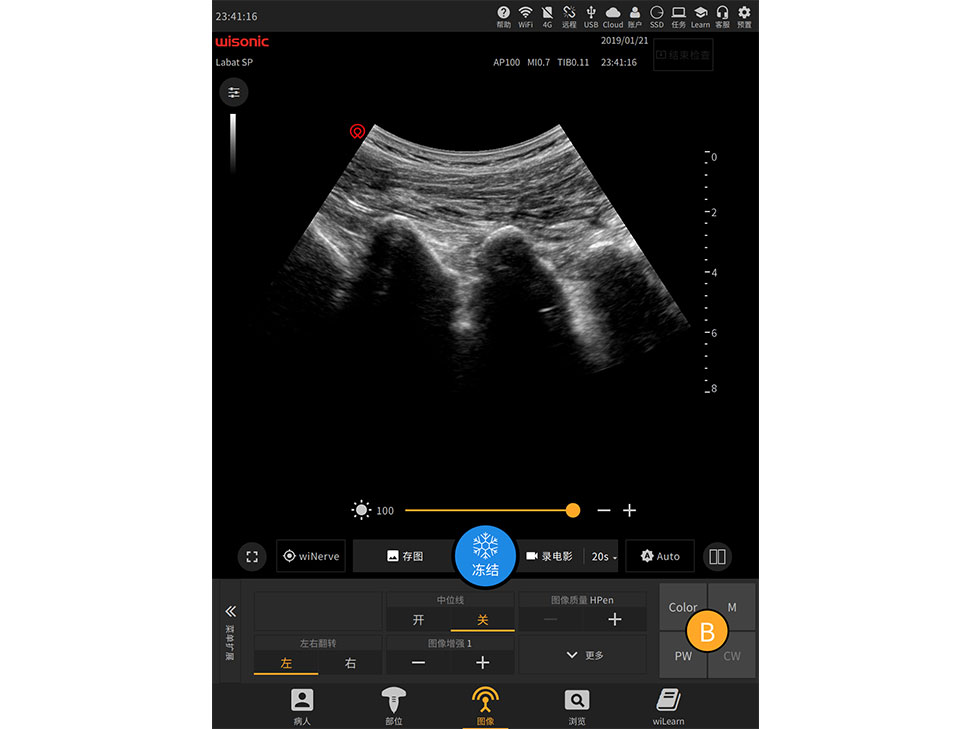

21.3

-inch Large Touch Screen Display

Anti-glare, full size, high sensitivity

Simplified Control Panel

Built-in fingerprint sensor, and smooth trackball

Full Touch Screen Display

Support Liquid Disinfection

Multi-touch Operation

Minimal Panel for Clinical Customization

High Sensitivity Waterproof Trackball

Anti-splash

Multi-function Joystick